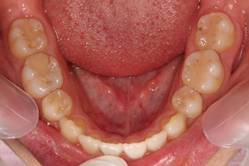

インビザGOによる矯正症例1 16歳男性

マウスピース矯正開始前。右上犬歯が内側にありました

前から見たところ

4か月後。犬歯が外側に出てきました

治療終了後10か月